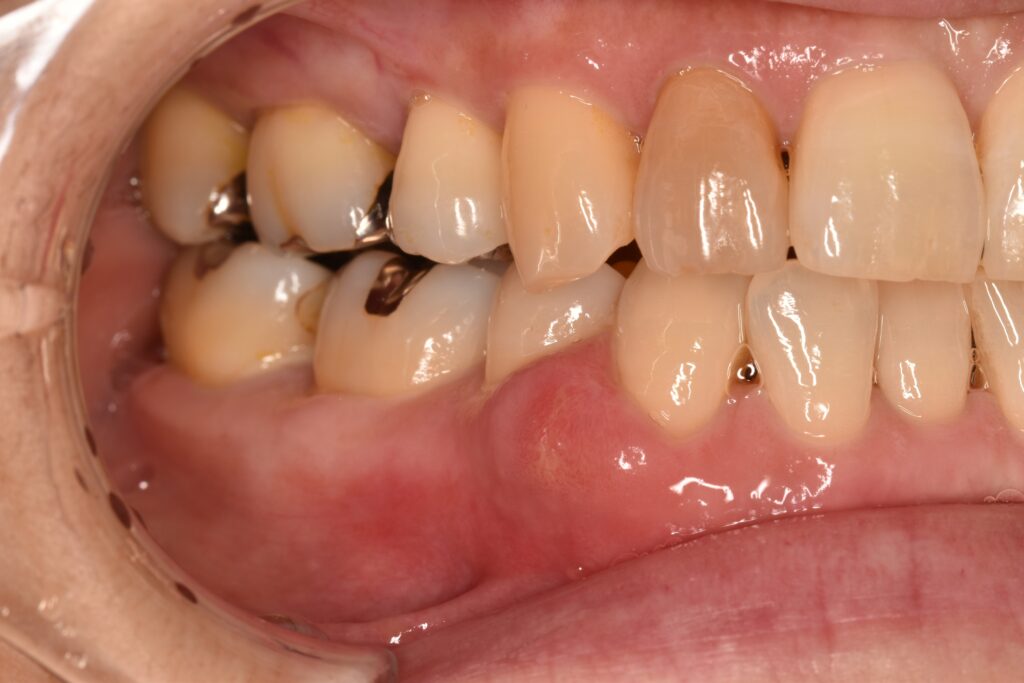

こんな感じで歯肉が大きく腫れている患者さんが来院されました。

まずは歯間ブラシで歯肉のチェックです。

ん?歯周病かな?でも歯間ブラシの状態は良い感じ。なぜ腫れているのか…